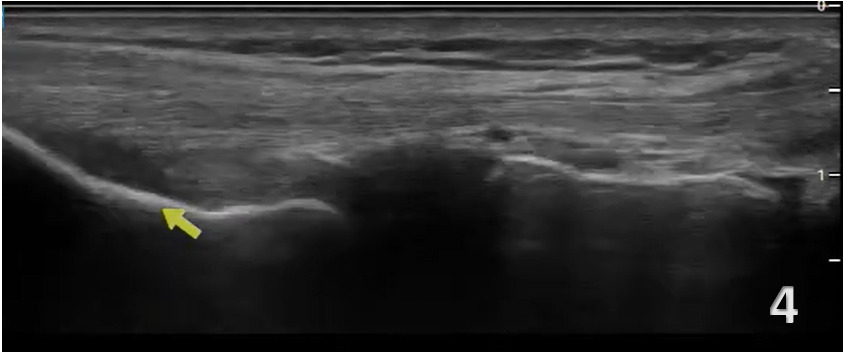

Normal Sonographic Appearance

In the LAX view, depending on the probe width and size, one should start distally to visualize the hyperechoic reflection of the bony cortex of the fibular head distally and the cortex of the femoral epicondyle more proximally. If the depth is increased enough, you will also be able to visualize the bony reflection of the tibia directly below the fibular head. Usually, the LCL demonstrates a hyperechoic fibrillar pattern. The distal portion of the tendon may appear heterogeneous and thickened due to the bifurcating distal biceps femoris tendon that runs both superficial and deep to the LCL.9

Patient Position: The patient is supine with the hip internally rotated and the knee in slight flexion (35-40 degrees). A bolster or towel roll can be placed under the medial knee for support. The probe is placed in either the short axis (SAX) or longitudinal axis (LAX), starting proximally near the lateral femoral epicondyle or distally at the fibular head.